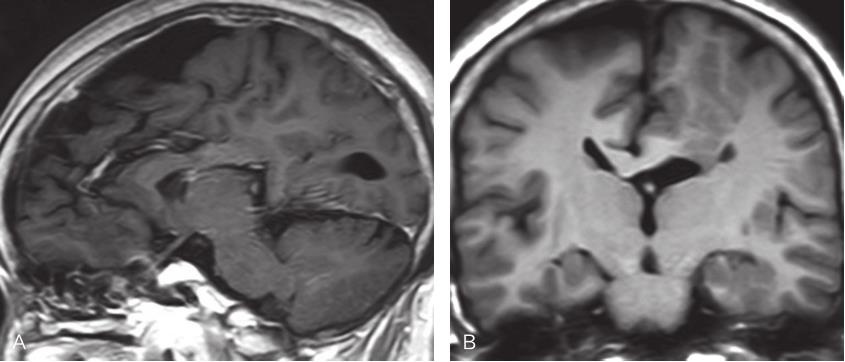

图2-3-2 胼胝体完全缺失MRI表现

A.矢状位T 2 WI示胼胝体完全性缺失,第三脑室扩张并向上移位,扣带回呈放射状分布,胼周动脉垂直向上走行;B.冠状位T 1 WI示脑纵裂池向下延伸至第三脑室顶,侧脑室呈“公牛角”样改变;C、D.横断位T 2 WI示双侧侧脑室平行分离,侧脑室后角及三角区扩张,侧脑室前角变窄,第三脑室扩张并上移位至分离的两侧侧脑室之间